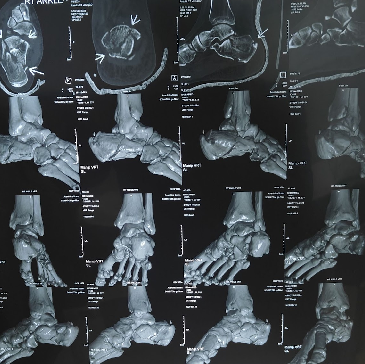

Undisplaced / Hairline Fracture Treatment in Perambur

Hairline fractures occur when the bone develops a small crack but remains properly aligned. Most heal successfully without surgery through immobilization, rest, and regular monitoring.

Treatment approach includes

- Diagnosis of minor bone cracks and stress fractures

- Immobilization of the injured area

- Pain relief and inflammation control

- Monitoring bone healing progress

- Gradual return to normal activity

POP (Plaster of Paris) Immobilization Treatment in Perambur

Plaster of Paris is used to stabilize fractures that do not require surgical fixation. It keeps the injured bone in alignment and protects healing tissues.

POP treatment includes

- Stabilization of fractures using plaster cast

- Protection of injured bones during healing

- Prevention of movement that may worsen injury

- Monitoring cast condition and fracture recovery

- Guidance for safe removal and rehabilitation